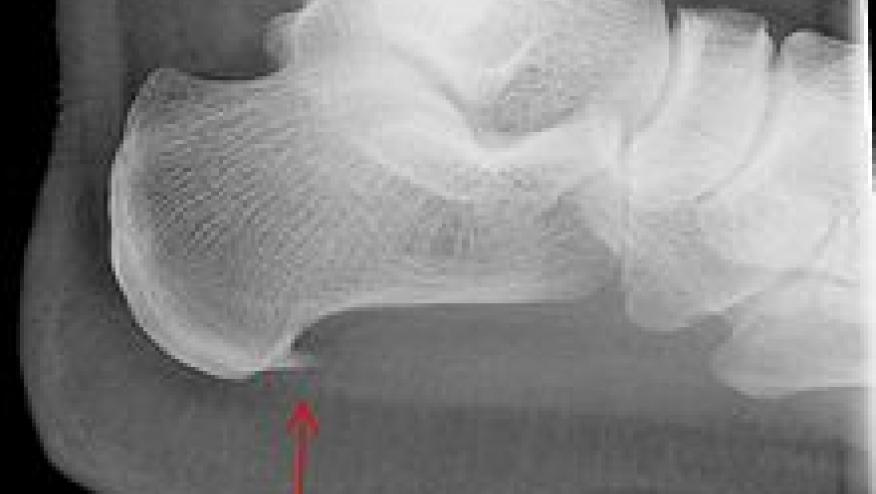

Calcaneal Fractures: Stress fractures usually manifest as progressive pain following an increase in activity level or walking on hard surfaces. These are often due to repetitive stress, strenuous exercise/sports (especially runners) or heavy manual work. At risk individuals include runners (may also get metatarsal stress fracture) and those with osteoporosis. These are diagnosed by MRI (early) or plain radiography (late) and usually located inferior and posterior to the posterior facet of the subtalar joint. Clues include pain at rest, local ecchymosis, point tenderness at the fracture site.

This particular patient had lateral calcaneal pain. Based on the above, her differential diagnosis may include calcaneal stress fracture, entrapment neuropathy (lateral plantar nerve) or the sinus tarsi syndrome.